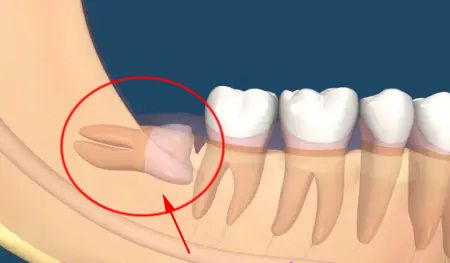

很多人不知道,智牙這樣拔才科學!2021-07-30

很多人不知道,智牙這樣拔才科學[ 查看詳細 ]

很多人不知道,智牙這樣拔才科學!2021-07-30

很多人不知道,智牙這樣拔才科學[ 查看詳細 ]